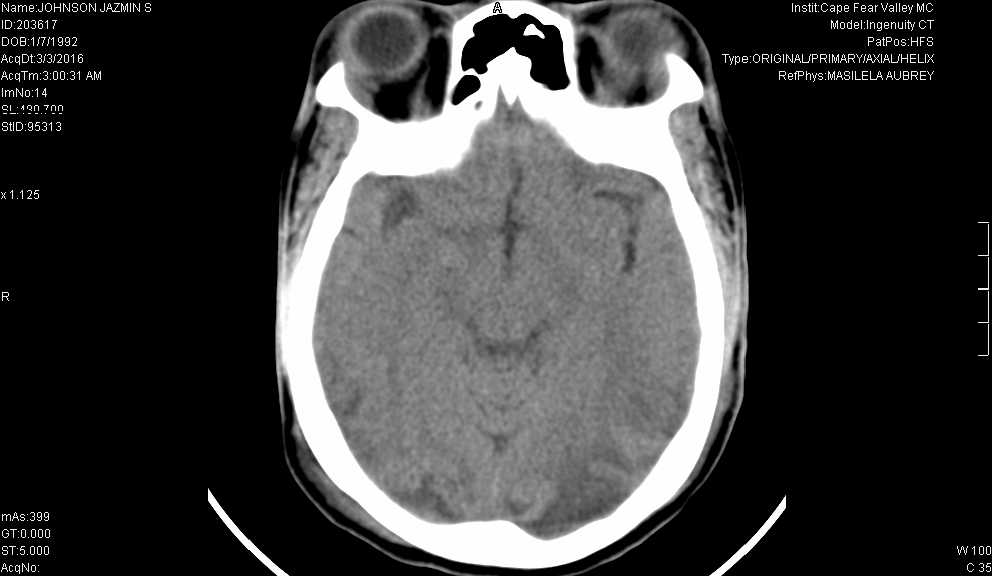

A 24-year-old African American female with a history of polysubstance abuse presented to the emergency department in status epilepticus. The patient was given Midazolam by EMS. She arrived unable to protect her airway and was therefore intubated and sent for a non-contrast head CT. The patient’s mother denied a history of seizures, but reported her daughter complained of a headache earlier that afternoon. Past medical history was significant for SLE, depression, fibromyalgia, and medication non-compliance. Initial vitals revealed she was afebrile, pulse of 87, blood pressure of 150/96, and respiratory rate of 30. Within the first hour, her blood pressure climbed to 167/120 and her pulse to 153. Her initial CT scan is shown below:

Comorbid medical conditions, including ischemic bowel disease, sepsis, hyponatremia, and proteinuria, may exacerbate neurologic deterioration, and therefore are important to identify early. Neuroimaging is critical to the diagnosis of RPLS. Typical findings are symmetrical white matter edema in the posterior cerebral hemispheres, especially the parieto-occipital regions. However, variations are common. These abnormal findings are often apparent on CT scans, but are best visualized on MRI. Because there are no specific diagnostic criteria for RPLS, recognizing the clinical symptoms and signs, identifying comorbid conditions, and rapid assessment of laboratory and imaging studies is key.